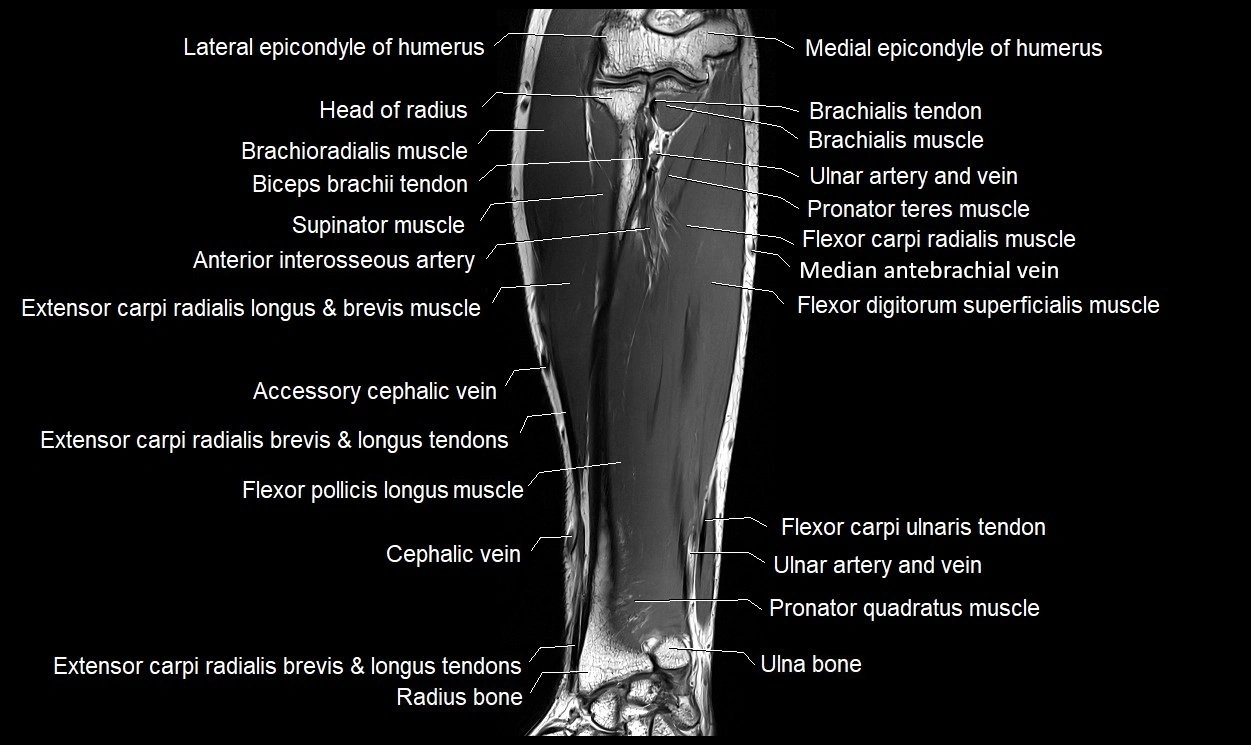

MRI images

image